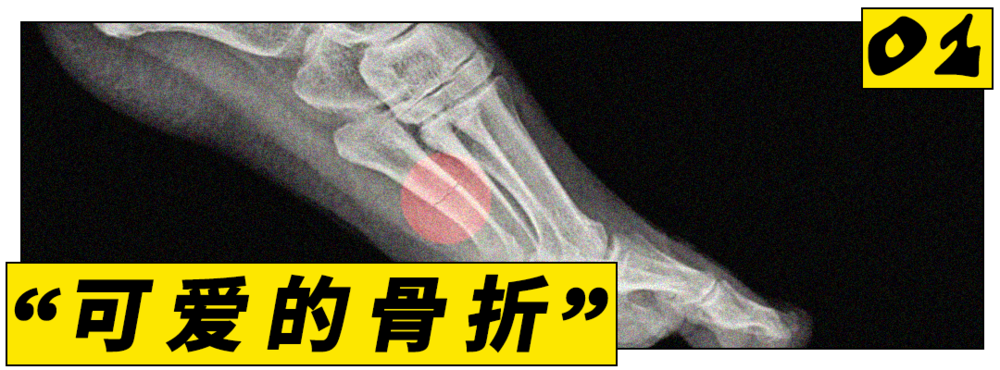

21世纪,跑步的火爆程度早已超出了一项运动本身。要问2026年跑步圈最火的话题是什么,应力性骨折一定榜上有名。

用一句话概括的话,它是由长期运动所引发的微小骨裂,也或许是今年最流行的伤痛。根据Google搜索趋势,今年关于应力性骨折的关注度已创下了自2004年以来的新高。

这可能意味着,我们即将见证人类史上第一个骨折潮流。

骨折不是稀事,但奇怪的点在于,过去会患上应力性骨折的往往是专业的跑步选手。据统计,大约40%的运动员在一辈子里至少会得一次应力性骨折。

一篇学术报告也指出,这种骨折常见于精英运动员和军事训练人群。这些人的下肢会长期承受重复性冲击负荷,一般人几乎没可能不会受这样的伤。